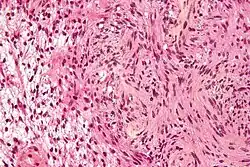

| Micrograph of a schwannoma | |

Schwannomas are mostly benign tumors that commonly occur in individuals with NF2 and schwannomatosis (sometimes called neurofibromatosis type III). Schwann cells are glial cells that myelinate the axons of nerve cells. Myelin is a lipid covering that speeds the conduction of action potentials. When Schwann cells proliferate out of control in an encapsulation it is called a schwannoma. Although schwannomas are benign they become detrimental when the growing tumor compresses the nerve. Schwannomas on sensory nerve axons cause chronic severe pain. Treatment options for schwannomas are to surgically remove them, have radiation, cyberknife or intracapsular enucleation. Previous designations for schwannomas include neurinoma and neurilemmoma.[3]